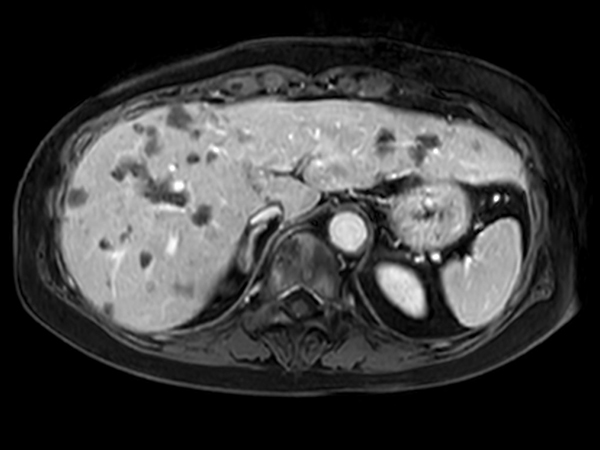

Axial eTHRIVE 90 sec Post gado